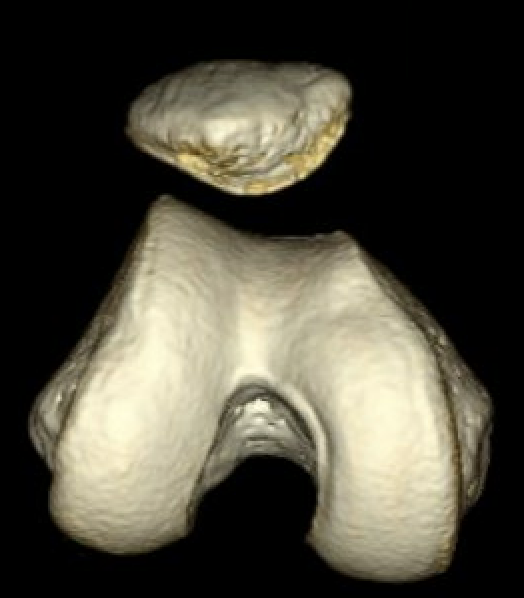

Trochlea dysplasia

Lateral subluxation / trochlea dysplasia